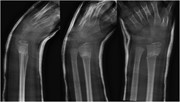

Desmoplastic fibroma of the distal radius: an interesting case and a review of the literature and therapeutic implications

Kathleen S. Beebe and Joseph A. Ippolito

Journal of Surgical Case Reports, Volume 2016, Issue 1, January 2016, rjv171, https://doi.org/10.1093/jscr/rjv171